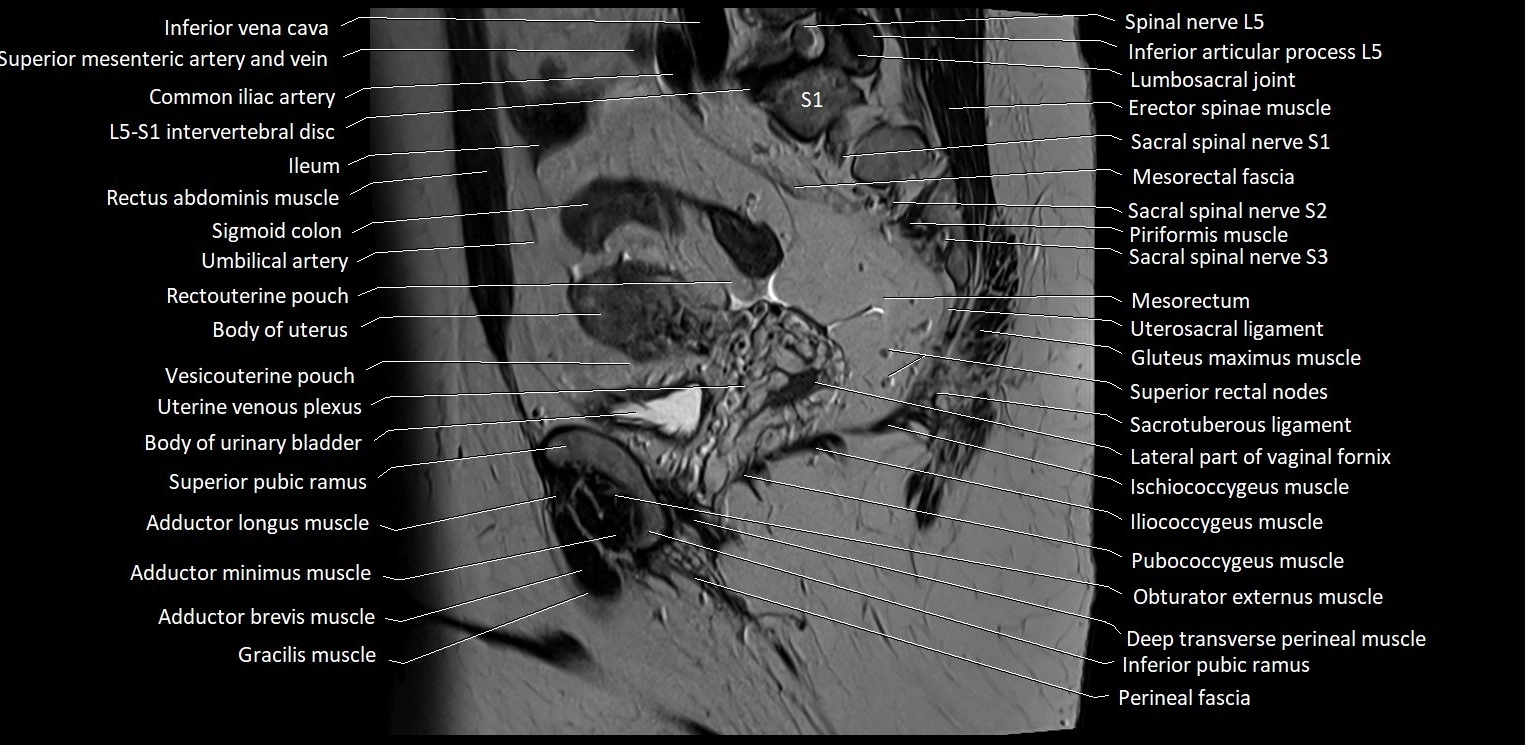

- Body of uterus

- Ileum

- Mesorectal fascia

- Mesorectum

- Piriformis muscle

- Pubococcygeus muscle

- Rectouterine pouch (pouch of Douglas)

- Sigmoid colon

- Umbilical artery

- Uterine venous plexus

- Uterosacral ligament

- Vesicouterine pouch